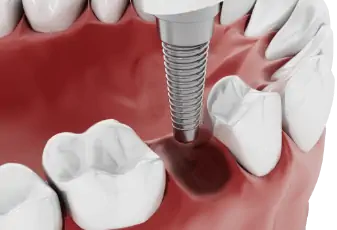

השתלת שיניים

השתלת שיניים - המדריך עם כל המידע הרפואי והמעודכן בזכות מודעות גוברת לחשיבות השמירה על היגיינת הפה, רובנו נהנים משיניים בריאות לאורך זמן. מובן שרפואת שיניים מניעתית אין בכוחה לבטל כל צורך בהתערבות כגון סתימת חורים בשיניים, טיפולי שורש וע